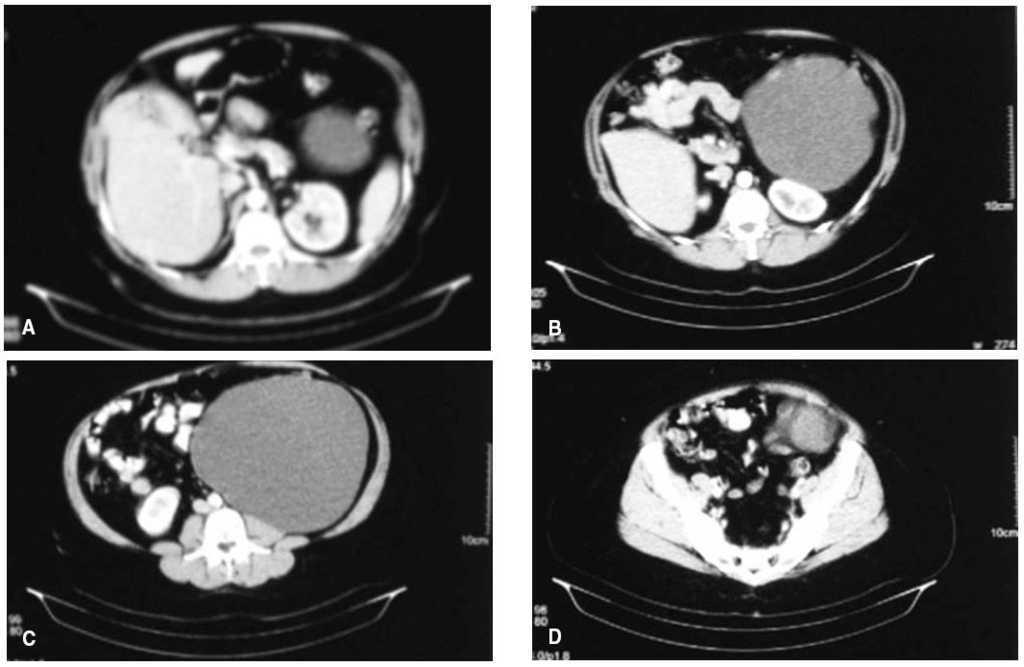

La lesión permaneció estable hasta 2007. Entonces la ecografía muestra una lesión quística de 23 µ 16 cm, en el vacío izquierdo y aparentemente retroperitoneal, sin depender del riñón ipsolateral. La TC abdominopelviana objetiva una estructura quística de 24 µ 18 cm, de paredes finas, sin septos, con dos pequeños polos sólidos y de localización retroperitoneal, en contacto con el riñón izquierdo y el psoas, pero independiente de éstos (fig. 1). El estudio analítico era normal (alfafetoproteína y CEA normales).

Fig.1.A:polo superior de la tumoración.B:corte a nivel de contacto con páncreas y riñón izquierdo.C:corte a nivel de contacto con músculo psoas.D:polo inferior de la tumoración.